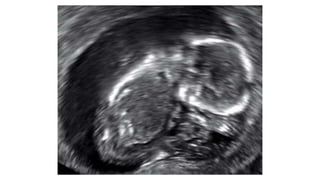

2. Ectopic Pregnancy

An ectopic pregnancy occurs when a fertilized egg implants and

grows outside the main cavity of the uterus. An ectopic

pregnancy most often occurs in a fallopian tube, which carries

eggs from the ovaries to the uterus.

> occurs when gestation is located outside the uterine cavity/tubal

pregnancies

 >Ultrasound